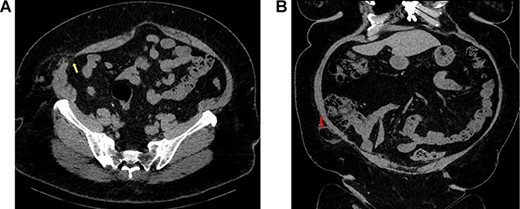

A contrast CT scan of her abdomen and pelvis was performed, this demonstrated a right sided Spigelian hernia with a 15 mm neck with the appendix and a small amount of fat within the hernial sac and caecum lying against mouth of the hernia intra-abdominally (Fig. 1 A and B).

(A) Axial view of CT abdomen and pelvis demonstrating Spigelian hernia with an abdominal wall defect through all three layers of abdominal wall (yellow arrow); (B) coronal view of the same scan demonstrating the appendix herniating through the defect in hernial sac (red arrow).